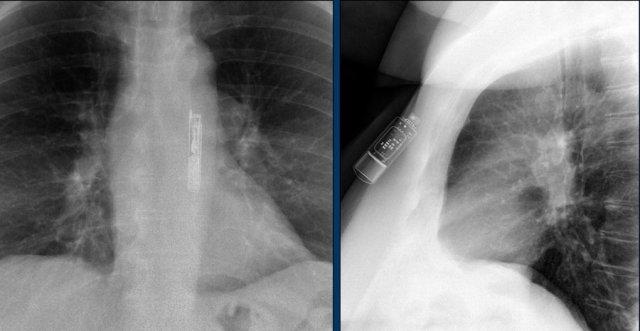

Điện cực tạo nhịp thượng tâm mạc

Điện cực thượng tâm mạc thường được đặt trong quá trình phẫu thuật tim nhằm cho phép tạo nhịp tim sau phẫu thuật.

Một số trung tâm đặt điện cực này cho tất cả bệnh nhân phẫu thuật tim, trong khi các trung tâm khác chỉ đặt cho những bệnh nhân có rối loạn nhịp tim trong lúc phẫu thuật.

Sau vài ngày, điện cực có thể được rút ra bằng cách kéo đơn giản.

Đôi khi điện cực được để lại tại chỗ.

Các điện cực thượng tâm mạc lưu lại dường như không gây nguy hiểm cho bệnh nhân trong môi trường MRI.

Tuy nhiên, kết luận này chủ yếu áp dụng cho các khảo sát MRI ngoài tim.